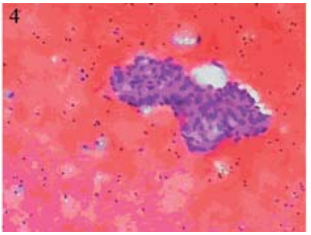

于2012年11月5日在B型超声定位下行肝包膜下 囊性包块穿刺引流,引流液暗红色不凝血,查穿刺 液常规:颜色:暗红色,红细胞计数:150×109/L, 白细胞计数:600×109/L,中性粒细胞70%,淋巴 细胞30%,李凡他试验+,透明度:浑浊。生化: 总蛋白:50.1 g/L,乳酸脱氢酶:1 042 IU/L。肿 瘤指标:CEA:958 ng/ml,CA125:788.2 IU/ml, CA199:>195 9 IU/ml,AFP:5.8ng/ml。脱落细胞 学检查找到癌细胞,见图 4。引流后于2012年11月9 日予顺铂40 mg囊腔内注射,治疗后复查肝脏B型 超声:肝包膜下囊性占位明显缩小,大小约0.8 cm ×0.8 cm,见图 5。

图 4 肝包膜下巨大囊性转移瘤患者脱落细胞学检查 Figure 4 Cytology of huge cystic metastatic tumor of hepatic subcapsular Cancer cells were found |